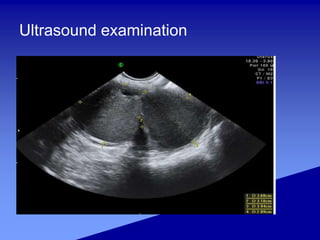

Ultrasound examination